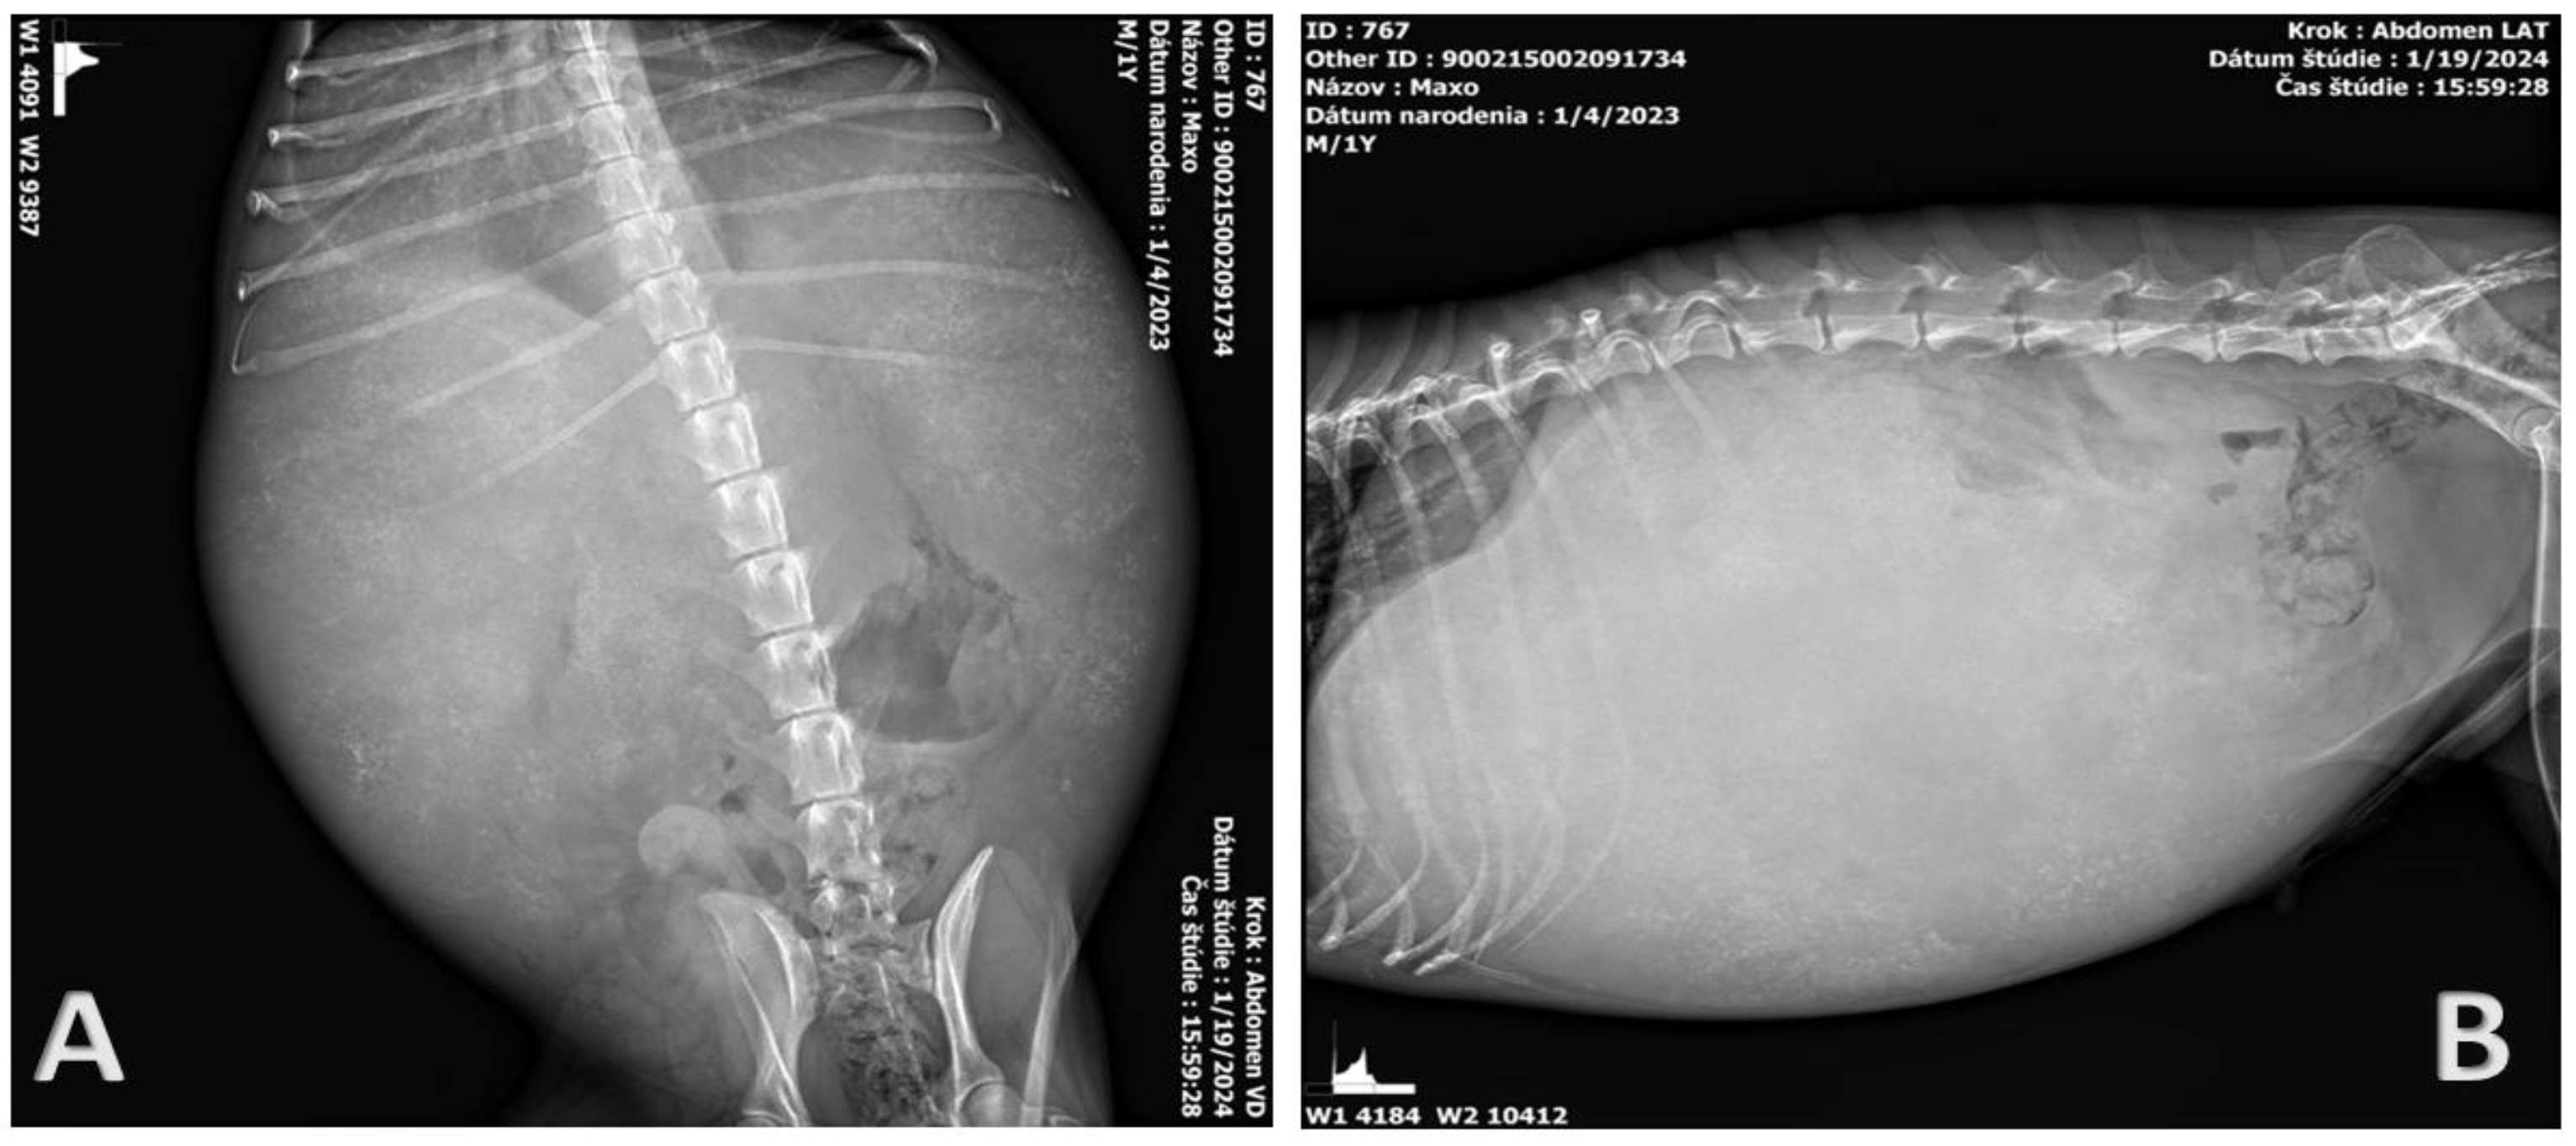

2.2. Clinical Examination